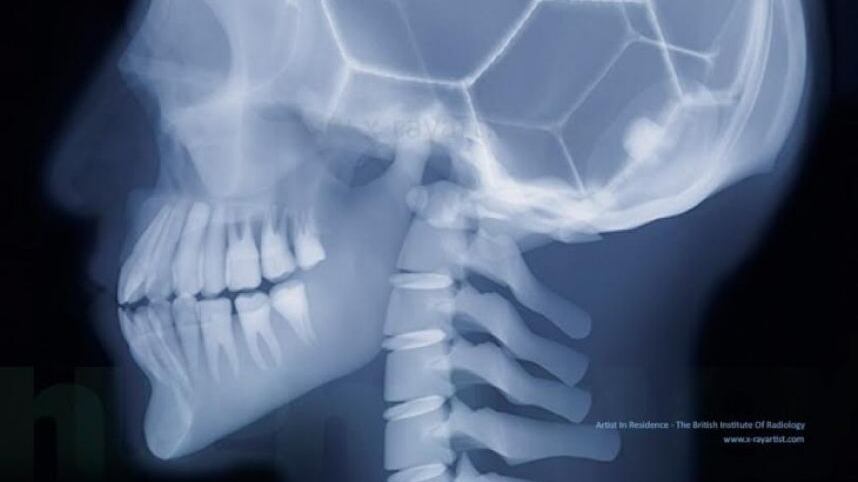

Gracias a una tomografía computarizada de alta resolución, los investigadores lograron detectar indicios de este tumor en los restos óseos de una mujer hallada en el cementerio neolítico de Stuttgart-Mühlhausen, y han descartado que pudieran estar provocados por otras patologías similares.

En concreto, encontraron una pérdida inusual de tejido en el interior del hueso, lo que se conoce como hueso esponjoso, en restos de su húmero y esternón, según ha explicado Heike Scherf, uno de los autores del hallazgo.